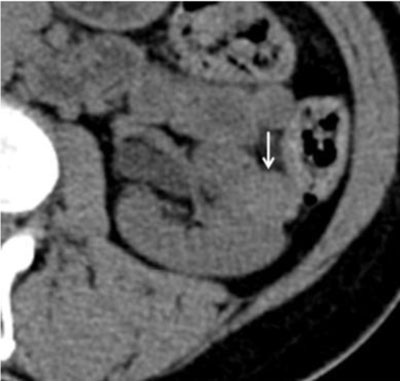

Figure 3

UECT demonstrating a left solid renal lesion (arrow). It appears homogeneously hyperdense and has attenuation values as high as 44 HU, consistent with fat-invisible AML [9].